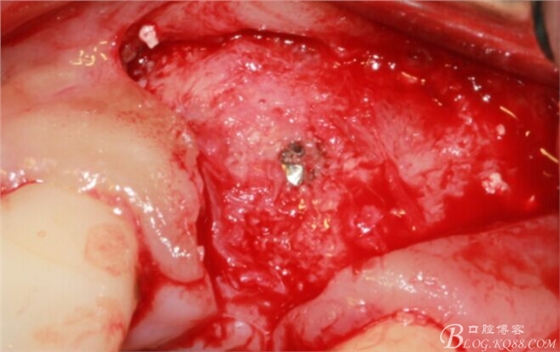

再次翻瓣。

先行粘骨膜減張,取自體血液。

根方用取骨鉆取自體骨。

旋入一長兩短3顆鈦釘。